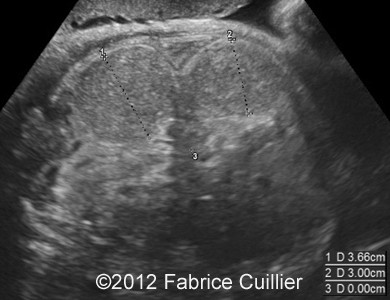

At 28 weeks, ultrasound examination revealed an abnormal fetus, with moderate polyhydramnios, moderate ileal and jejunal dilatation (Image 1) with normal peristalsis. There was no pyelectasy. There were no other dysmorphologic signs of aneuploidy. There was no sign of meconium peritonitis. There was no sign of congenital infection. The maternal serological status did not show any sign of maternal infection (TORCH and Parvovirus B19). Our first hypothesis of diagnosis was congenital chloride or sodium diarrhea. But sodium and chloride level in amniotic fluid were normal (results from first amniocentesis).

Image 1: At 28 weeks and 29 weeks, moderate ileal and jejunal dilatation.